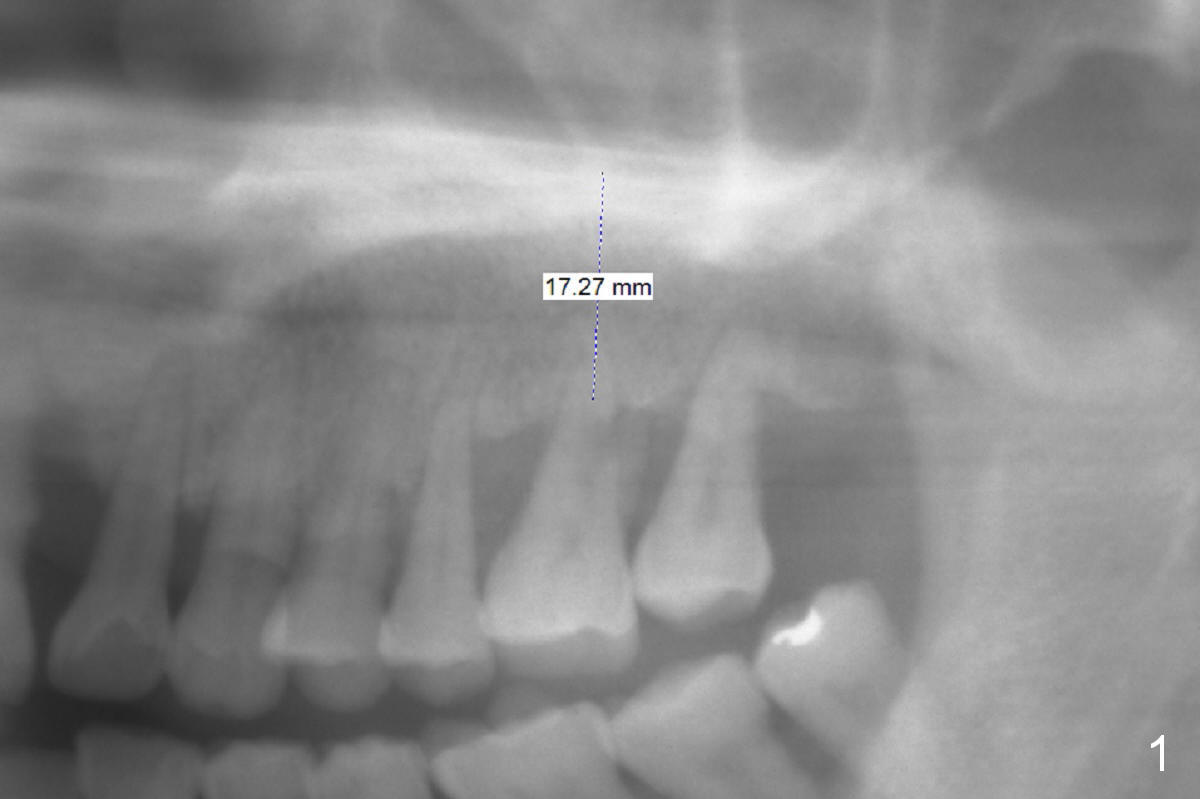

The teeth #14 and 18 of a 46-year-old man become symptomatic 1 month after #4 implant placement. While the socket at #14 is shallow, the apical bone is abundant (Fig.1). The longest IBS implant should be safe (13 mm, Fig.2). In contrast, the socket at #18 is relatively deep, the apical bone is short (Fig.3). A shorter implant (11 mm or less, Fig.4) should be chosen. Osteotomy in the new bone should be 4 mm. Try in a 5x9 mm dummy implant at #18. No antibiotic is used for socket treatment. The bone density in the mandible should be high (drills), whereas that in the maxilla may be low (expanders) or medium (drills). Preop exam will decide which tooth needs treatment first. Take photos PRN.